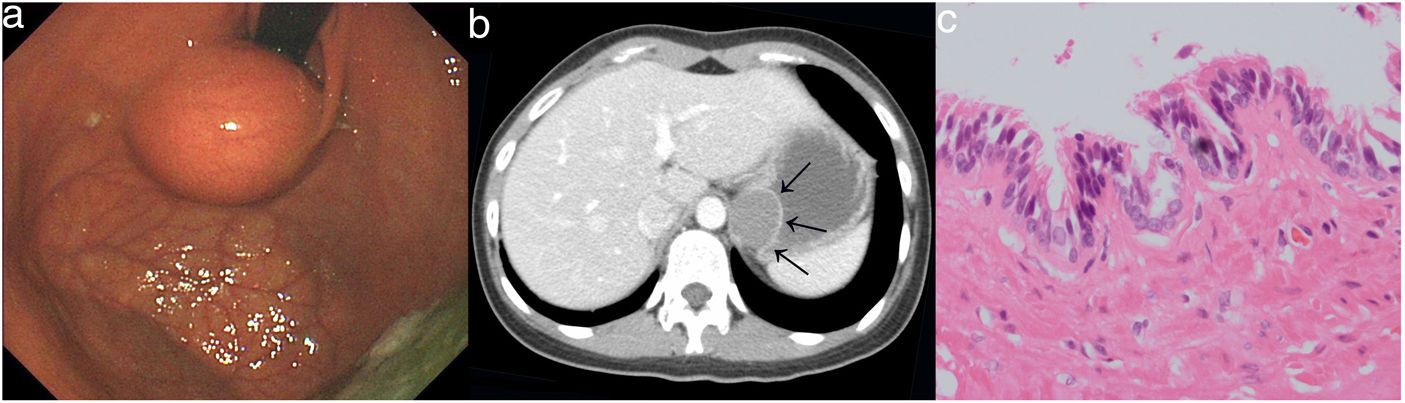

An 18-year-old woman presented with aggravated vomiting for 10 months, without remarkable past history. Both her physical examination and laboratory were normal. Upper endoscopy showed a soft spherical bulge with smooth surface in the gastric cardia and fundus (Fig. 1a). Endoscopic ultrasound demonstrated that the lesion was an extrinsic compression. Enhanced computed tomography scan was performed, revealing a low dense cystic lesion with wall enhancement (Fig. 1b, arrows). The lesion was found to be located in the abdomen, and was completely excised by laparoscopic surgery. Histologic findings reported the presence of ciliated pseudostratified columnar epithelium in the cyst wall (Fig. 1c, H&E 400×), thus an abdominal bronchogenic cyst was finally diagnosed. The patient was discharged without any complications. Her symptom was gone during follow-up.

(a) Endoscopic image. A soft spherical bulge with smooth surface in the gastric cardia and fundus; (b) computed tomography image. A low dense cystic lesion with wall enhancement; (c) histologic image (H&E, 400×). The presence of ciliated pseudostratified columnar epithelium in the cyst wall.